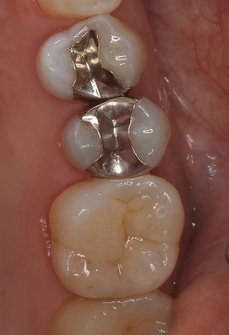

遠心縁下のカリエス処置

患者さんは50代男性

近医の先生からの紹介

親知らずの影響で第2大臼歯遠心にカリエスが出来てしまったということです。

幸い症状などはありません。

レントゲン

2026 EEdental MIH (1).jpg

かなり大きな虫歯があります。

患者さんにまず口腔外科で抜歯をしてもらい

術後3週間後に一度神経を残す方向でレジン充填を行い

痛みなどが出てしまったら、後で神経を取る処置を行なうと説明

患者さんにOKをもらい

2026 EEdental MIH (2).jpg

特殊な削り方をしてレジン(プラスチック)を詰めました。

親知らずの影響か、セメント質の肥厚が見られました。

かかりつけの先生がこういった道具で

カリエス除去用チップ | 歯科器具の超音波スケーラー・エアスケーラー用チップなら有限会社錦部製作所

遠心縁下の虫歯治療が出来ると知っていたことが幸いでした。

一般的な治療はこんな感じで

2026 EEdental MA.jpg

大きく削って神経取っても、見えない為に虫歯は残したまま・・・

ホントこの部位の虫歯の治療は知っている・知っていないで大きく差が出てしまいます(>。<)